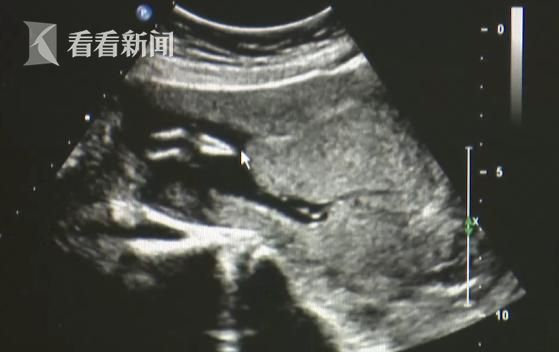

袁志宏发现,胎儿的小腿骨好像有点交叉。 正常的小孩子,下肢应该是不停地在妈妈肚子里动的 ,呈现外八字形。

胎儿已经三个月,袁志宏再三观察,发现胎儿的小腿一直没有活动。尽管有着20多年的超声科经验,这种情况,袁志宏也是第一次见。

袁志宏表示,胎儿的小腿基本上是有点融合的,周边软组织好像也是融合的。

袁志宏怀疑,这是传说中极为罕见的“美人鱼综合症”,立马让孕妇再去产科确认。

经诊断, 胎儿是多发畸形,人鱼综合症并发的,合并其他的畸形。